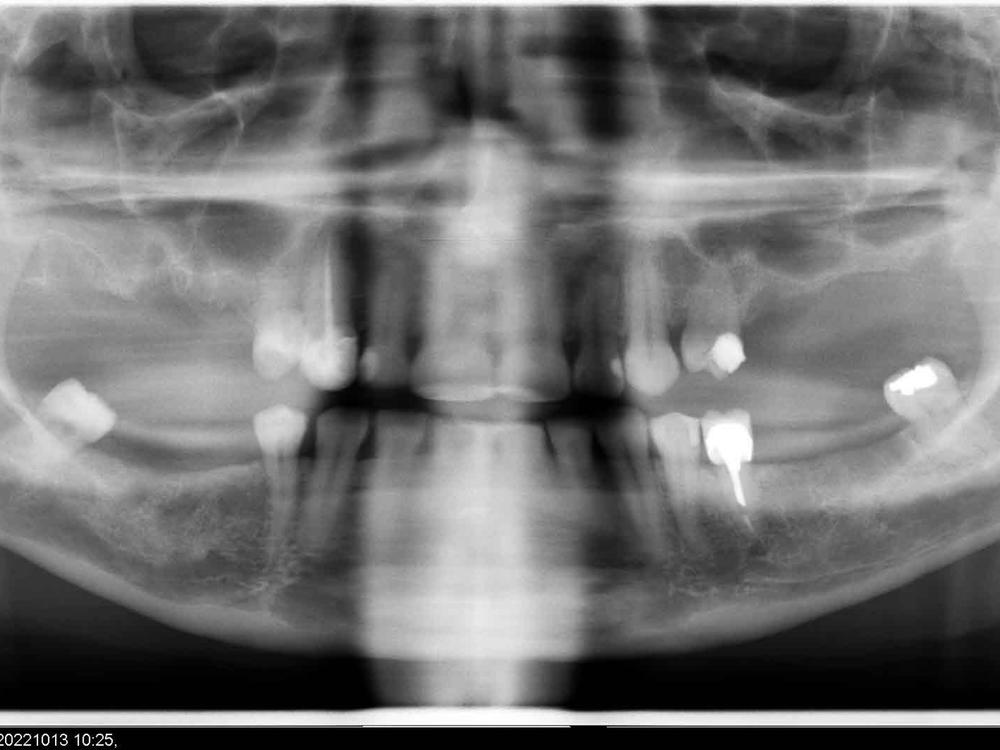

18 months ago I was the victim of medical negligence at the hands of a dentist who extracted 3 teeth in such a way that left me with nerve damage and PTSD. The resulting damage to my jaw and remaining teeth meant I lost 7 more teeth last year, and have been in constant pain ever since. I have since found an amazing dentist who has done his very best to fix me and figure out why I react so badly to dental procedures and why I am in so much pain, but I still have no answers. With no end to the pain in sight and my remaining teeth still so problematic, the best option is to have them all removed and replaced with full dentures. I have been quoted over $10,000 to have this done, and I have already spent close to $8000 over the last 18 months and have no savings left. Please help me put an end to my terrible pain and get new teeth.

Upper and lower dentures, extractions of my remaining teeth and sedation for this.